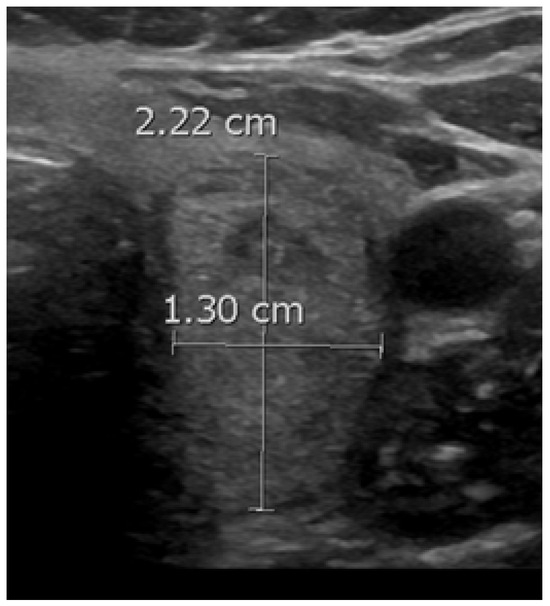

Figure 3. A benign nodule with a taller-than-wide shape.

When a thyroid nodule has an anteroposterior (AP) dimension that exceeds its transverse (TR) dimension such that the ratio is greater than 1, it is classified as having a taller-than-wide shape (Figure 3). This observation was first reported in 2002 by Kim et al. in a study involving 155 thyroid nodules with an average size of 7.5 mm, of which 49 were malignant. This study found that a taller-than-wide shape was associated with a 92.5% specificity and 32.7% sensitivity for malignancy [51]. The authors proposed that this taller-than-wide configuration may reflect an underlying tendency for malignant nodules to grow across tissue planes, unlike benign nodules, that grow along tissue planes [51]. A meta-analysis and a systematic review by Brito et al., examining 31 studies and 18,288 nodules with an average size of 1.5 cm, reported that a taller-than-wide shape was associated with an OR of 11.1 (95% CI, 6.6 to 18.9) for malignancy [52]. In our study, we observed a significant association between a taller-than-wide shape and malignancy for nodules <1 cm but not for those above this size. For nodules <1 cm, a taller-than-wide shape was observed in 66.7% of malignant nodules compared to 5% of benign nodules (p = 0.03). In comparison, for nodules ≥1 cm, a taller-than-wide shape was seen in 14.6% of malignant nodules versus 13% of benign nodules (p = 0.67). Other studies have found similar findings [53,54]. In a study involving 207 nodules, of which 110 were malignant, Ren et al. found that a taller-than-wide shape was a good predictor for papillary cancer for nodules ≤1 cm but not for larger nodules [53]. In a study involving 1238 nodules, of which 159 were papillary cancers, Kim et al. found that a taller-than-wide shape was associated with an OR for cancer of 2.7 (95% CI, 1.7 to 4.3) (p < 0.001) for nodules ≤1 cm vs. an OR of 1.2 (95% CI, 0.4 to 3.2) (p = 0.77) for nodules >1 cm [54].